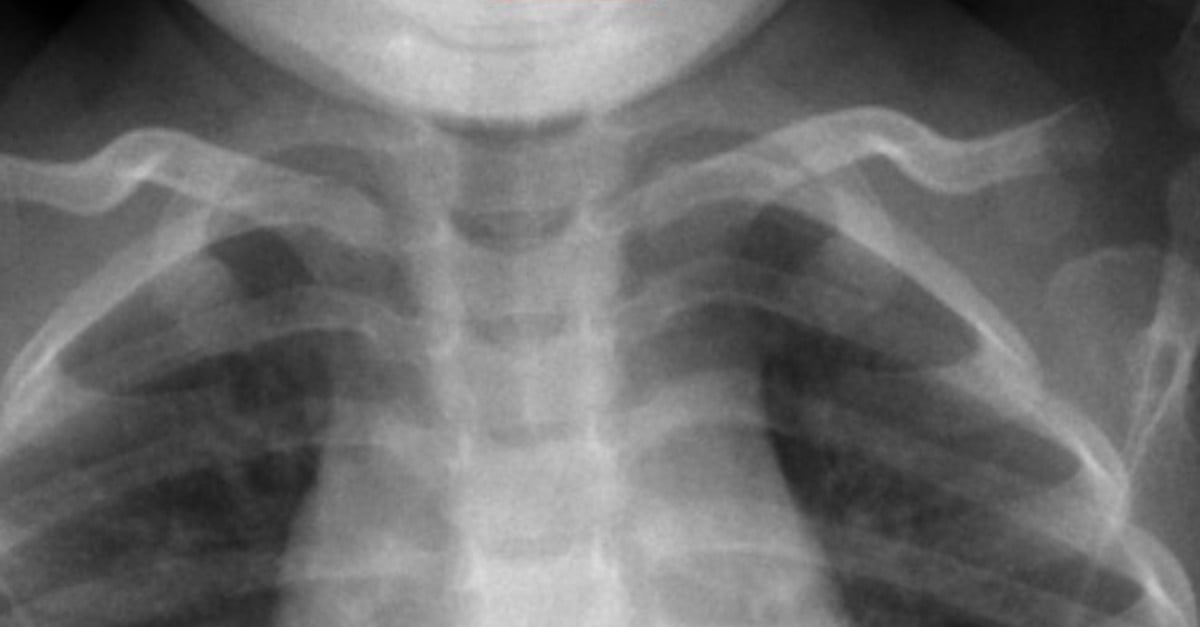

From www.apsf.org

Perioperative Management of Button Battery Ingestions in Children Are Lithium Button Batteries Dangerous there is an emerging danger hiding in your home — lithium batteries, also known as button batteries — causing injuries and death in children. the risks of button batteries. When button batteries come into contact with saliva or. an increasing number of little children are eating small lithium batteries, also known as “button” batteries, that power many. Are Lithium Button Batteries Dangerous.